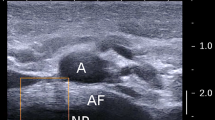

The AF comprises 15–25 concentric lamellae of collagen fibers embedded in a proteoglycan matrix. Annulus fibers are oriented at 45°–65° to the spinal axis, with fibre direction alternating between consecutive lamellae (Fig. 1). The AF acts in tension to restrain the increasing fluid pressure in the nucleus when the spine is compressed, and it is sufficiently rigid to stabilise the spine by resisting bending, torsion and shear. Typically the AF fails in tension, when combined loading in compression and bending forces pressurised nucleus tissue through a fissure growing radially outwards in the AF, usually posterior to the nucleus [1]. Such a disc herniation can cause back pain and sciatica.

Cadaveric discs were divided into the following regions for testing: nucleus pulposus (NP), anterior annulus (A), anterolateral annulus (AL), lateral annulus (L) and posterolateral annulus (PL). The posterior annulus (P) was generally too thin and disrupted for testing. The inset image shows that small specimens were prepared approximately parallel to one of the annulus fiber directions (indicated by the blue line). Note that the curvature of annulus lamellae in an intact disc is reduced when the disc is first divided into regions, and nucleus pressure is lost. This altered geometry reduces collagen fibre disruption in the small excised specimens

Each disc was divided with a scalpel into nucleus pulposus (NP), anterior AF, anterolateral AF, lateral AF and posterolateral AF. Each region was further divided into inner, middle and outer parts (Fig. 1). The posterolateral AF was only divided into inner and outer sub-regions because the radius here is relatively small. AF from the posterior midline was excluded because many samples were small, disrupted and dehydrated. The innermost AF was defined by the presence of the first discernible lamellae, and the outer-most AF was defined by the presence of only longitudinal fibers from the longitudinal ligaments. A cutting device with parallel razor blades was used to obtain 1.5 mm-thick slices of AF, from which specimens were cut parallel to one of the fiber directions (Fig. 1). Tissue was partially frozen so the geometry remained regular. Specimens were wrapped in cling film to minimize water loss. Then, cyanoacrylate adhesive was used to fix both ends of each slice to strips of sandpaper with the rough surface outside (Fig. 2) so it could be gripped securely. The width, thickness and length (between sandpaper edges) were designed to be 1.5 mm × 1.5 mm × 5 mm, and the exact dimensions of each specimen were measured after cutting and adhesion using a Vernier caliper (accuracy 0.1 mm). A digital display minimized specimen deformation during measurement. To reduce errors, all dimensions were measured twice (by two investigators) and then averaged.